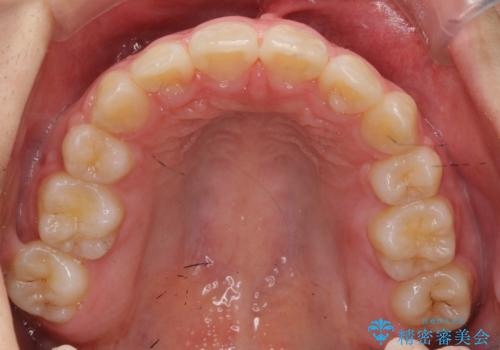

- 前歯のがたがたを主訴に来院。

口元も下げたいとのことでした。

成人式の1年前から矯正をはじめ、成人式前に上の前歯の装置を一時的にとりました。

一時的に装置を取ることで、多少治療期間が伸びましたが、それでも、2年かからずに外すことができました。